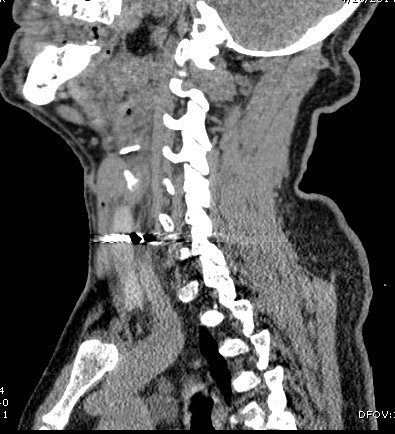

CT Neck showed metallic foreign body piercing the right sternocleidomastoid muscle at the level of lower border of C6 vertebral body, likely abutting the carotid sheath at the level of lower border of cricoid cartilage on right side of neck. Soft tissue density anterior to IJV and CCA -likely haematoma

A CT Thorax was done which showed the metallic pellet migrated through internal jugular vein into inferior

venacava atrial junction.